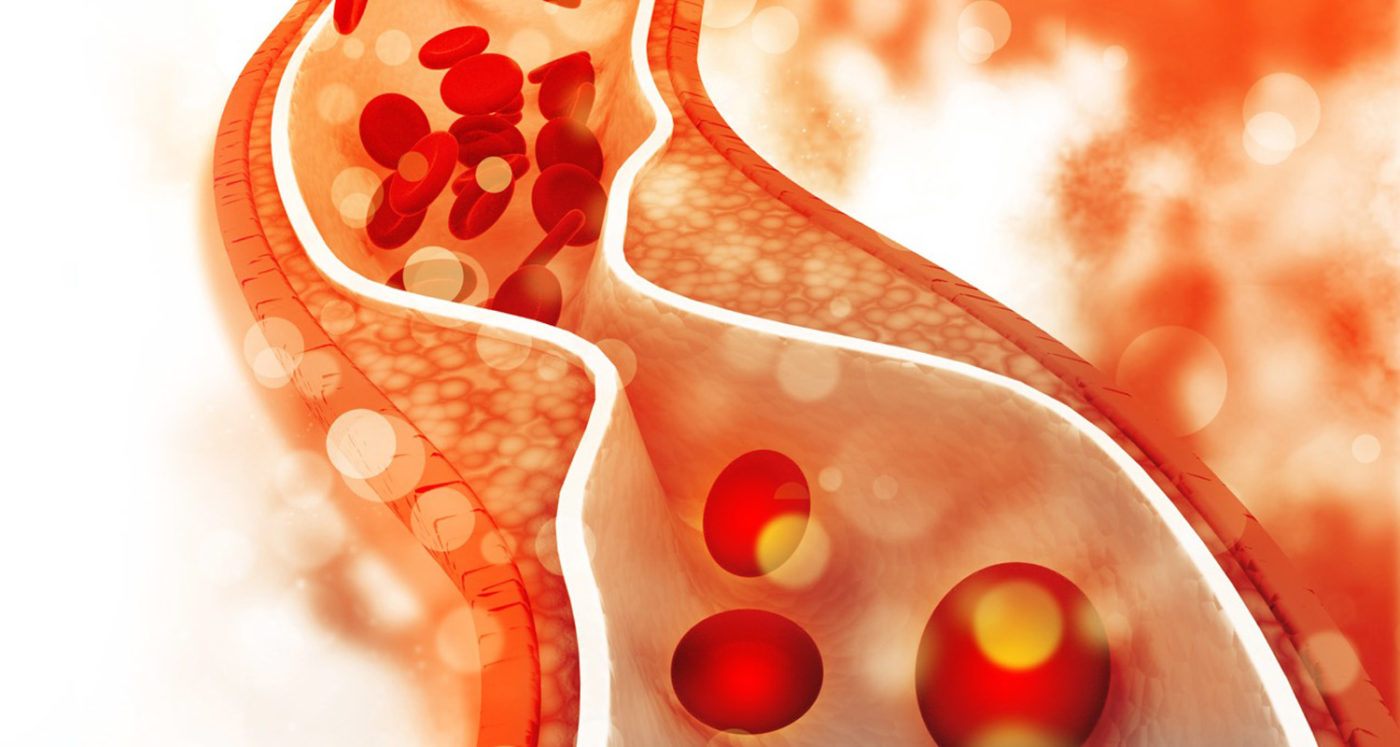

Fabbisogno giornaliero di steroli vegetali Assumere un quantitativo sufficiente di steroli vegetali aiuta a tenere a bada il colesterolo e bisogna condurre una dieta equilibrata per avere la certezza che siano abbastanza. Ma cosa sono esattamente gli steroli vegetali? Scopriamo nel dettaglio l’importanza che hanno questi lipidi nel nostro organismo. Cosa sono gli steroli vegetali […]